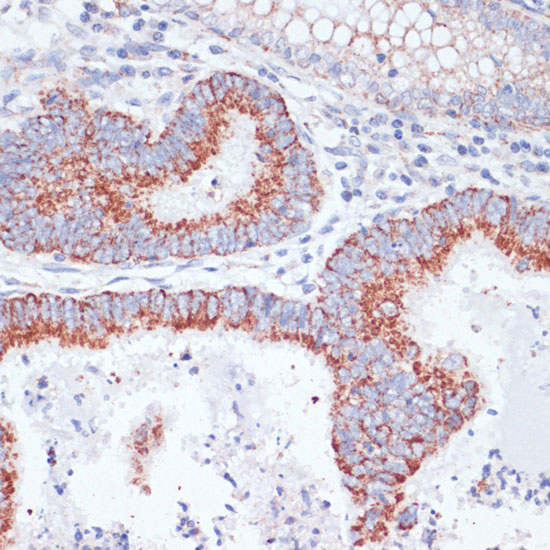

DescriptionTFRC Polyclonal Antibody. Unconjugated. Raised in: Rabbit.

ApplicationWB, IHC, IF, IP